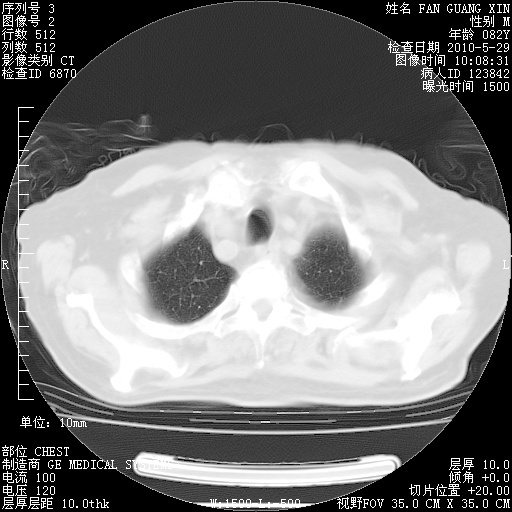

再治疗10天后的肺部CT 纵膈窗